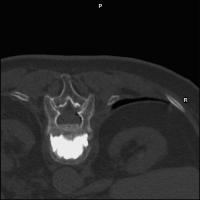

Vollbildansicht

Vertebroplastie - Zementpistole

Abbildung 4: Zementpistole nach Gangi [6] mit Druckentlastungshebel und großem Luer-Lock-Anschluß.

Keywords:

Foto

,

Mineralstoffwechsel

Wirbelkörperpunktion

Zementpistole